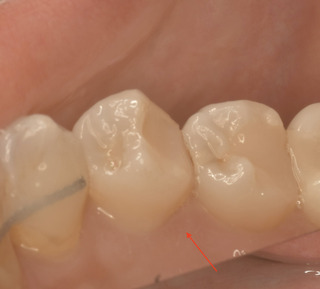

口腔内を見た状態 キレイにレジンが詰められていますね